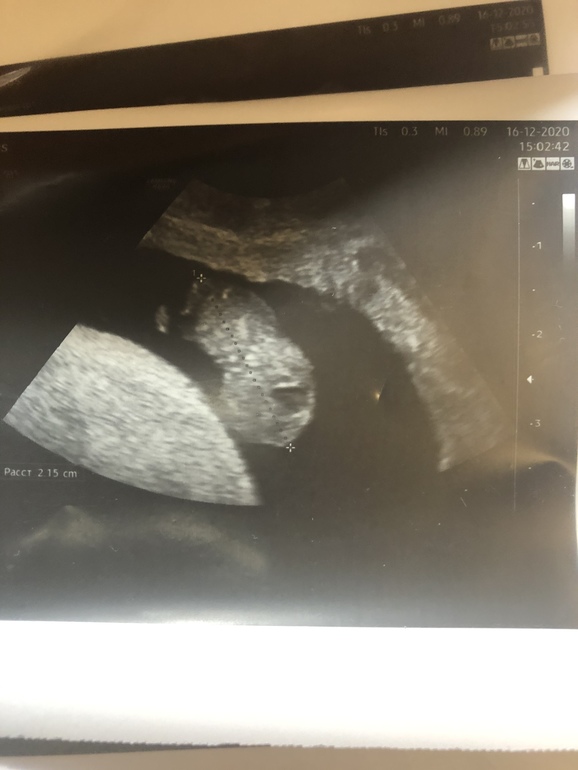

Как раз зашла Написать про узи и метод Рамзи . Может и мне кто-то сможет сказать ? 😊

15.12.2020

УЗИ в 7 недель Врач не поверила, что я на таком сроке нашла сердцебиение 😀